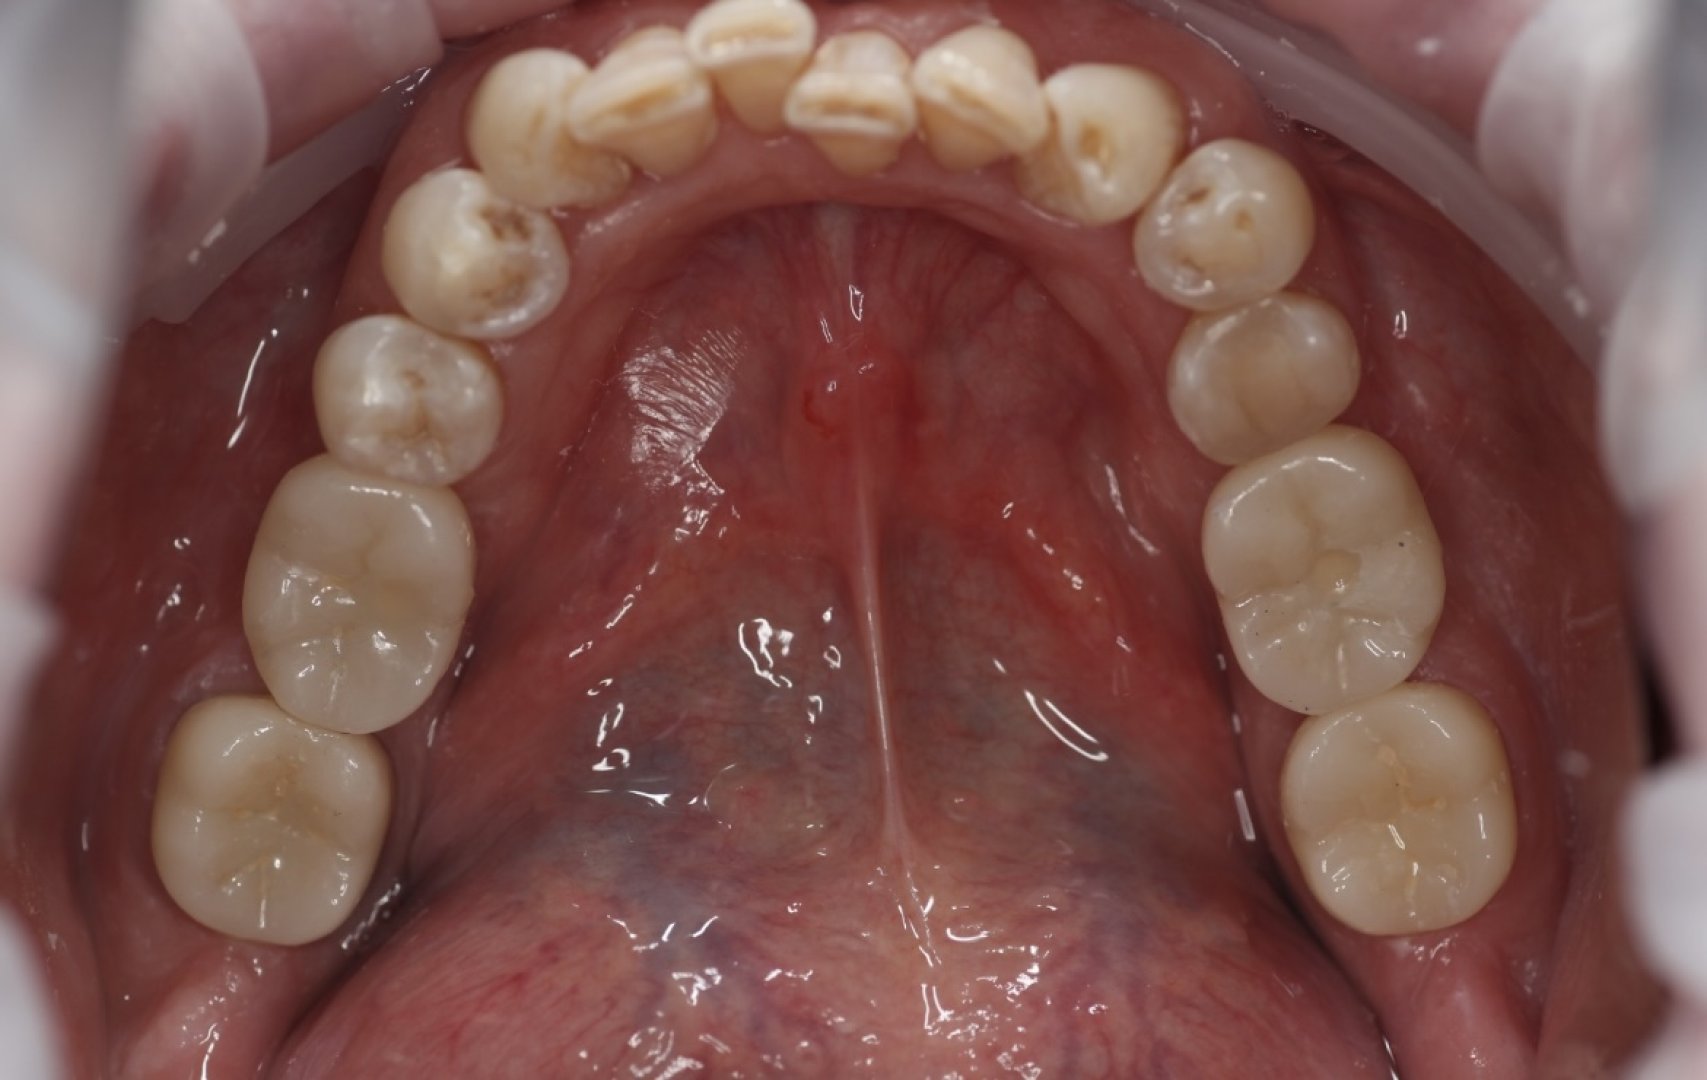

После препарирования и ретракции зубов 37 и 47, установки скан-маркеров и сканирования для изготовления будущих конструкций, были изготовлены прямым методом акриловые коронки 37 47.

Через 7 дней были установлены винтовой фиксацией коронки 36 и 46, коронки 37 и 47 зафиксированы с помощью сиц Fuji I.